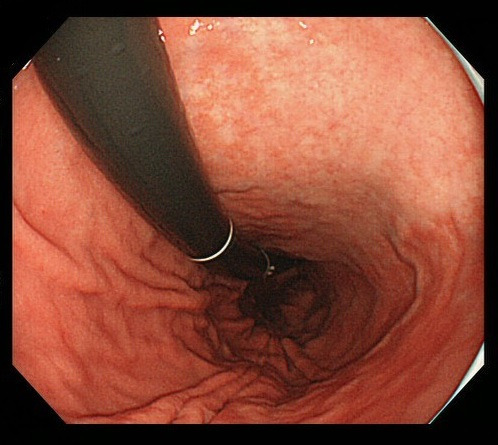

위내시경은 위 점막의 병변을 직접 확인할 수 있는 가장 정밀한 검사지만, 눈으로 보는 것만으로는 병의 본질을 100% 파악할 수 없습니다. 겉으로는 단순 염증처럼 보여도 실제로는 암세포가 존재할 수 있고, 반대로 악성처럼 보이는 병변이 양성일 수도 있습니다. 이런 시각적 한계를 보완하기 위해 시행되는 것이 바로 ‘조직검사’입니다. 조직검사는 위내시경 중에 의심되는 부위에서 작은 조직을 채취해 현미경으로 분석하는 과정으로, 세포의 형태와 배열, 염증 정도, 암세포 존재 여부 등을 확인해 최종 진단을 내립니다.